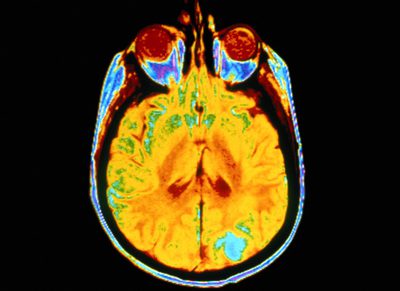

Il professor Garth Cooper dell'Università di Manchester, che guida il team di Manchester, afferma che l'accumulo di urea nel cervello, a livelli tossici, può causare danni al cervello e portare infine alla demenza.

L'urea e l'ammoniaca nel cervello sono prodotti della degradazione metabolica delle proteine. L'urea è più conosciuta come il composto che viene secreto dal corpo nelle urine. Se l'urea e l'ammoniaca si accumulano nel corpo, ad esempio perché i reni non sono in grado di eliminarli, possono verificarsi sintomi gravi.

La demenza provoca una perdita progressiva e irreversibile delle cellule nervose e del funzionamento del cervello, causando perdita di memoria e disturbi cognitivi che influenzano la capacità di apprendimento. Attualmente non esiste una cura.

Il team ha utilizzato cervelli umani, donati dalle famiglie per la ricerca medica, e pecore transgeniche in Australia. I membri del team di Manchester hanno usato la spettrometria di massa con cromatografia a gas, una tecnica di avanguardia, per misurare i livelli di urea cerebrale. Perché i livelli siano tossici l'urea deve aumentare di 4 volte o più rispetto al cervello normale, dice il professor Cooper.